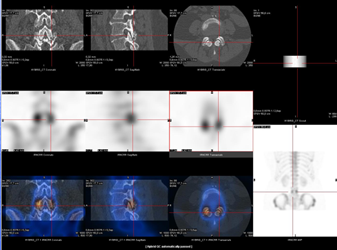

L’une des causes fréquentes d’hyperparathyroïdie est l’adénome parathyroïdien. La mise en évidence de cet adénome n’est pas toujours aisée et l’apport de la technique SPECT/CT est un bon atout diagnostique (2).

En effet, le SPECT/CT  apporte une valeur additionnelle en permettant  de guider le geste chirurgical. Le SPECT/CT permet d’identifier simultanément la zone métaboliquement pathologique et la localisation anatomique précise (profondeur du foyer et position par rapport aux structures environnantes et adjacentes). Ceci est illustré par la figure 6 qui met clairement en évidence un adénome parathyroïdien gauche.

Le SPECT/CT peut également être réalisé après une première chirurgie n’ayant pas abouti à l’exérèse d’un adénome, notamment pour rechercher une localisation ectopique.

Figure 6